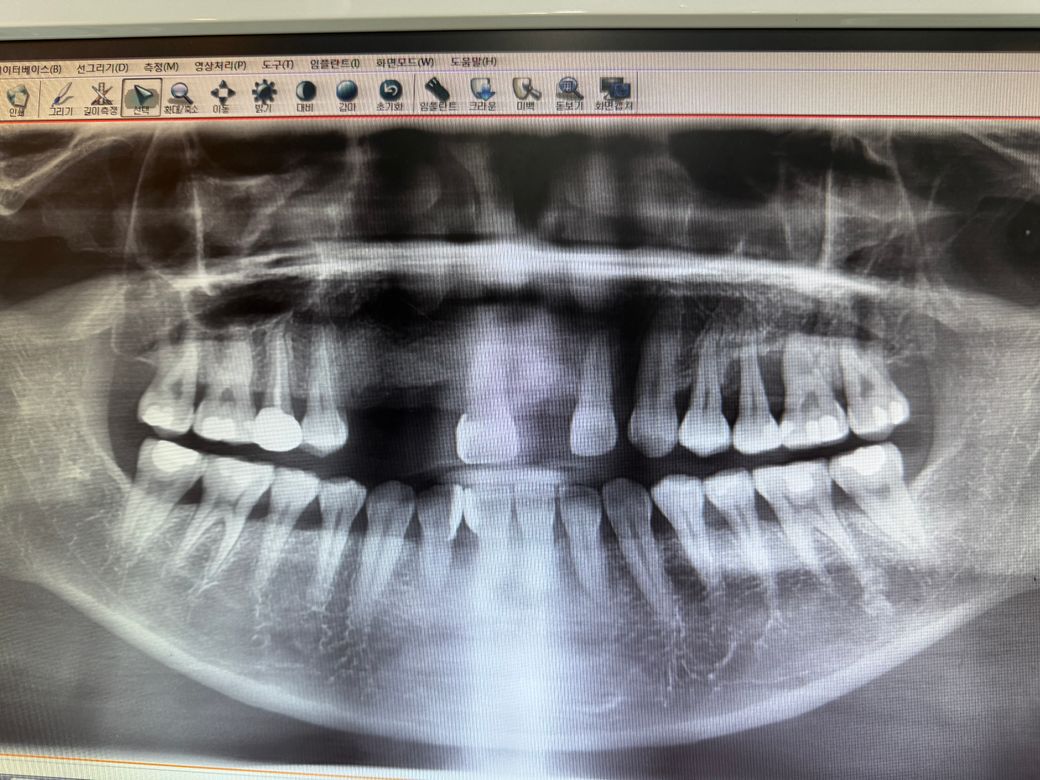

잇몸이 부어서 앞니 발치했는데 어금니도 발치해야할까요?

안녕하세요 저는 36살 여자입니다 잇몸이 붓고 가라앉고를 반복하다 앞니3개를 발치하고 뼈이식후 임플란트 대기중이에요 현재 지금 어금니쪽 잇몸이 부어서 상당히 아파요 ㅠㅠ 제가 췌장이식 받은지 10년차인데 면역억제제 복욕중이고 혈액투석중에 있어요 제가 궁금한것은 제 치아를 살려서 쓰고싶은데 선생님들의 견해마다 달라서 발치를 해야할까요? 최소 3개 라고 보시는거 같은데 부모님이 주신 하나밖에 없는 저의 영구치를 잃어야 한다는게 너무 속상해요

• 1번 째 사진

사진상에 오른쪽위 치아도 잇몸뼈가 많이 안좋은거 같습니다. 발치를 하시는게 좋을것같습니다.